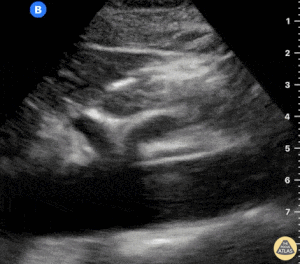

Ekokardiyografi (EKO): Anormal Patolojik Aort Örnekleri

Diseksiyon Flebi ile Sakküler Abdominal Aort Anevrizması

Abdominal Aort Anevrizmasının Sagittal Görünümü

Öksürük ile Başvuran Abdominal Aort Anevrizması

İntramural Trombüs İçeren Abdominal Aort Anevrizması